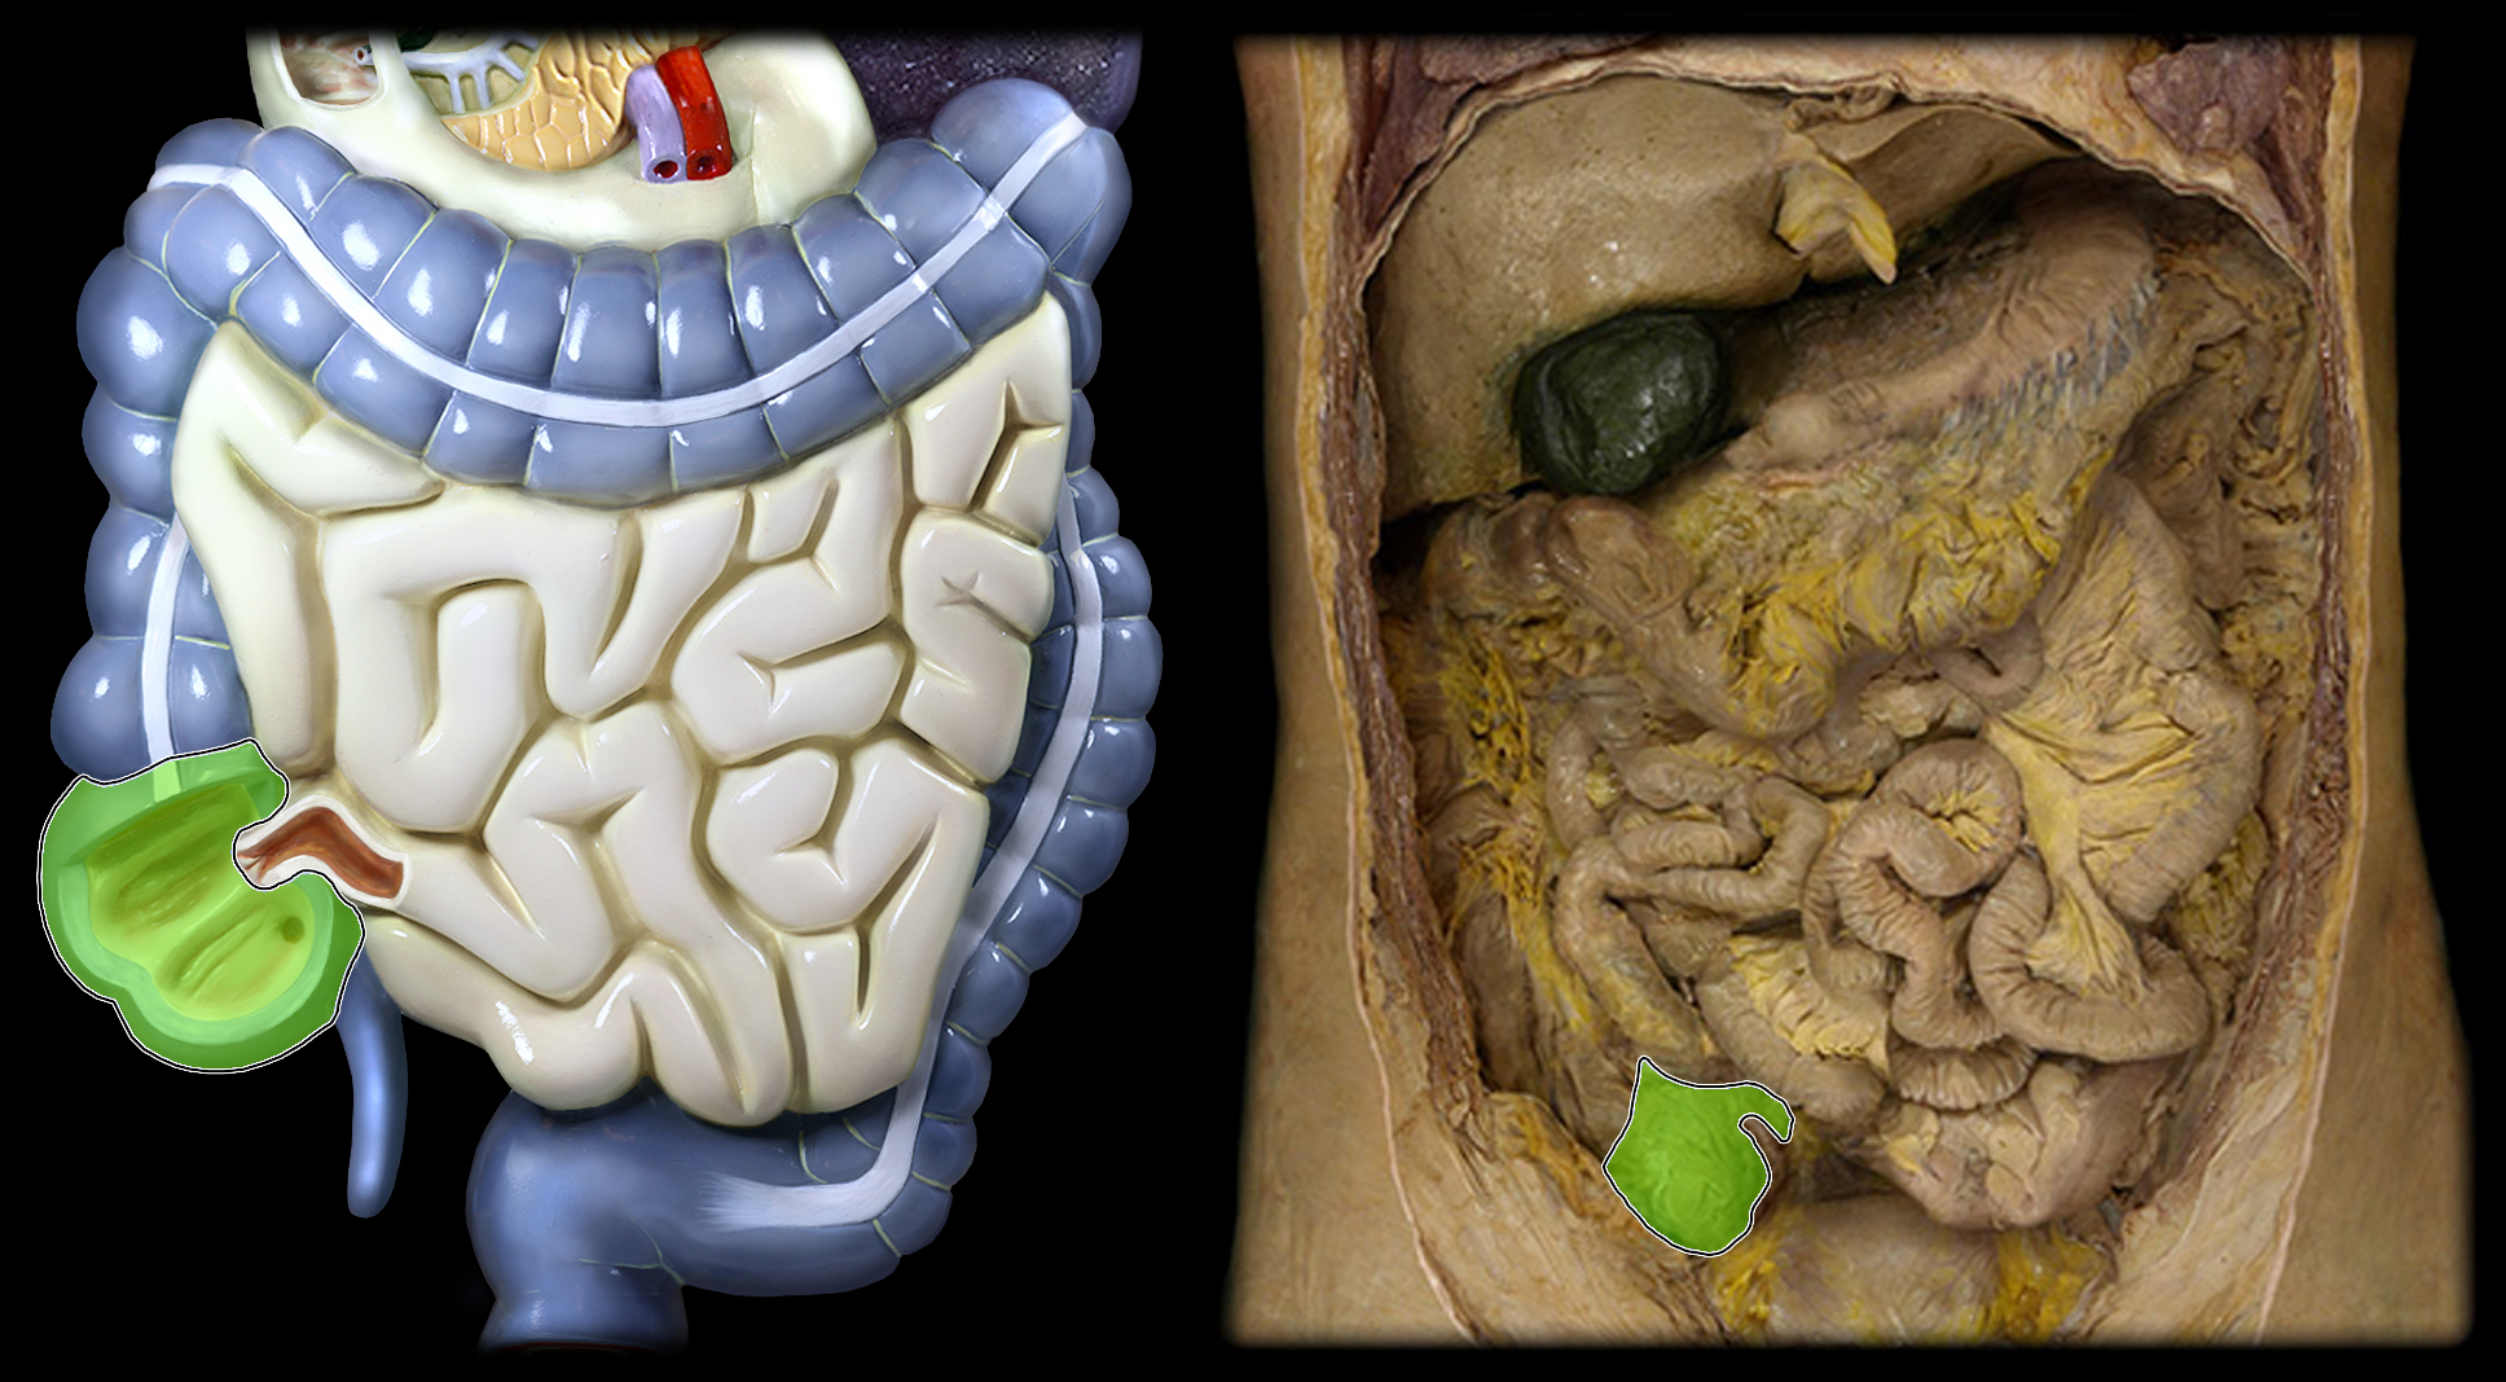

Cecum

Sigmoid colon

Jejunum

Ileum